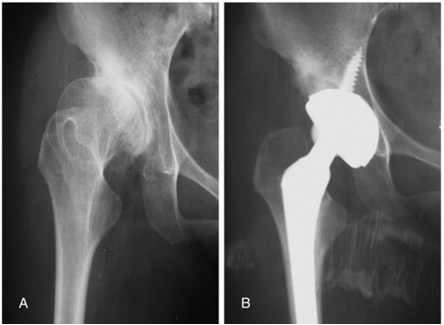

Quello che è certo però è che se non viene identificata precocemente, la lussazione dell’anca porta a una grave disabilità: il bambino zoppica per il risalimento della testa femorale sulla faccia esterna del bacino e più tardi l’adulto manifesterà molto presto i segni dell’artrosi rendendo necessario il ricorso alla protesi in età anticipata rispetto alla media della popolazione (fig. 3).

Fig. 3